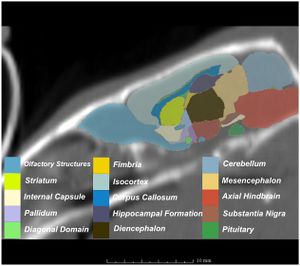

MRI with labeled structures from atlas registered to the CBCT. Registration was carried out with the open source imaging tool 3D Slicer, Version 4.4.0. |